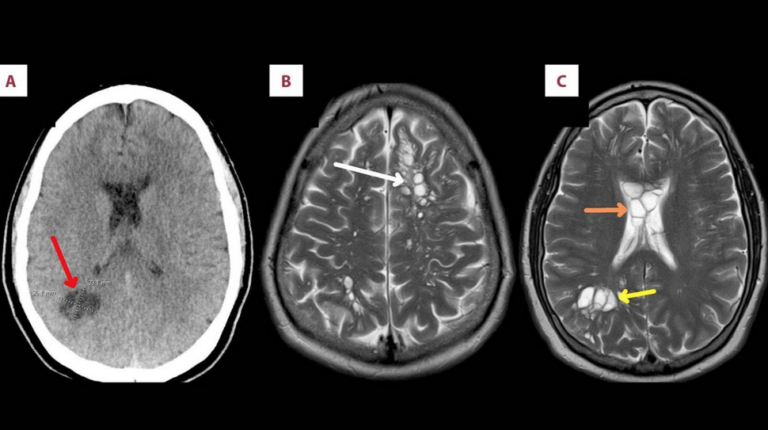

عمليات المسح كشفت وجود عدد من بيض الديدان الشريطية في دماغه (صورة نشرها الباحثون في المجلة الأميركية لتقارير الحالات الطبية) صحة العثور على بيض ديدان شريطية في دماغ رجل تناول لحم الخنزير المقدد by admin 14 مارس، 2024 written by admin 14 مارس، 2024 147 نيويورك: «الشرق الأوسط» عثر علماء على بيض ديدان شريطية في دماغ رجل أميركي كان يعاني من الصداع النصفي الشديد، وقالوا إنهم يعتقدون أن السبب في ذلك هو تناوله لحم الخنزير المقدد غير المطبوخ جيداً. وبحسب شبكة «سكاي نيوز» البريطانية، اشتكى الرجل البالغ من العمر 52 عاماً للأطباء من معاناته من صداع نصفي مستمر وشديد ولا يستجيب للأدوية. وكشفت عمليات المسح وجود عدد من بيض الديدان الشريطية في دماغه. وتم تشخيص إصابة الرجل بداء الكيسات المذنَّبة العصبي، وهو شكل من أشكال العدوى يحدث بسبب الديدان الشريطية التي توجد في لحم الخنزير غير المطبوخ جيداً. ويمكن أن تصل هذه العدوى إلى الأنسجة مثل العضلات والدماغ، وفقاً للباحثين الذين قالوا إن الرجل لم يسافر إلى أي مناطق مصنفة «شديدة الخطورة»، في ما يتعلق بهذه العدوى. وقال الفريق: «بعد مزيد من الاستجواب نفى المريض تناول طعام نيء أو طعام من الشارع لكنه اعترف بأنه اعتاد على تناول لحم الخنزير المقدد المطبوخ بشكل خفيف». وأشار الباحثون إلى أن أعراض الصداع النصفي تحسنت لدى الرجل بشكل ملحوظ عندما تم إعطاؤه أدوية مضادة للطفيليات والالتهابات. وأضافوا: «من غير المعتاد تماماً إصابة لحم خنزير بهذه العدوى في الولايات المتحدة، ومن ثم فإن حالة هذا الرجل تثير المخاوف بشأن احتمال وجود حالات أخرى مشابهة في البلاد». ووفقاً لمنظمة الصحة العالمية، يصيب داء الكيسات المذنَّبة العصبي في الغالب المجتمعات الزراعية الفقيرة، وهو السبب الرئيسي الذي يمكن تفاديه للإصابة بالصرع في العالم النامي. المزيد عن: الصحة صحة التغذية أميركا 0 comment 0 FacebookTwitterPinterestEmail admin previous post لأول مرة في العالم… اختبار علاج جيني لكبد بشري كامل ! next post حصيلة متواضعة لعام من التطبيع بين السعودية وإيران You may also like أعراض السرطان الصامتة: علامات خفية قد تكون قاتلة 28 أبريل، 2026 اختراق طبي: الذكاء الاصطناعي يكشف ألزهايمر بدقة غير... 11 مارس، 2026 طرق بسيطة لتخفيف أعراض التهاب المفاصل 11 مارس، 2026 سرطان الرئة الأكثر فتكا… والكشف المبكر ينقذ الآلاف 7 مارس، 2026 فتيات يقعن في فخ PPD مع موسم الحناء... 7 مارس، 2026 مفاجأة علاجية… عقار قديم يُظهِر فائدة جديدة للذاكرة 5 مارس، 2026 مسنون يقاومون الخرف: ما سر ذاكرتهم الخارقة؟ 4 مارس، 2026 تغييرات طفيفة في نمط الحياة تقلل من خطر... 26 فبراير، 2026 مارسه صباحاً ومساءً… نشاط يومي قد يبطئ السرطان 24 فبراير، 2026 (7 تغيرات) في الشخصية في منتصف العمر قد... 24 فبراير، 2026